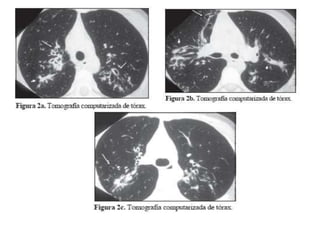

.    Mas de un 96% de los pacientes        broncopulmonares, son útiles los

de F.Q. fallecen por

complicaciones de una infección               percusion del tórax.

El objetivo en estos pacientes es la    (inhalada), para restablecer la

adherente y prevenir el avance de          eficacia para prevenir las

antibióticos reducen el numero de

bacterias en los pulmones de estos

pacientes.                BRONCODILATADORES AL MISMO

Rx. De tórax en un niño con F.Q.

Rx. De tóraxen un niño con F.Q.